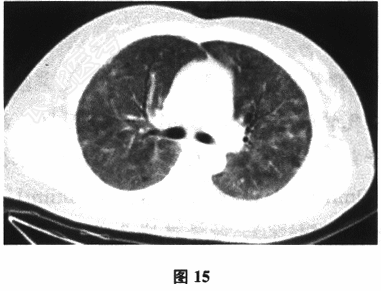

- 多项选择题2.[提示]患者入院后胸部CT检查见图15。为明确诊断还需进行下列哪些检查( )

- 多项选择题3.[提示]进一步检查结果:诱导痰培养结果阴性, 支气管肺泡灌洗液检出肺孢子菌包囊;动脉血气分析(未吸氧情况下): pH7.40,PO252mmHg(1mmHg=0.133kPa), PCO245mmHg,HCO-326mmol/L, BE2mmol/L;GM试验阴性; 血肌酐检测:40μmol/L。目前患者应诊断为( )